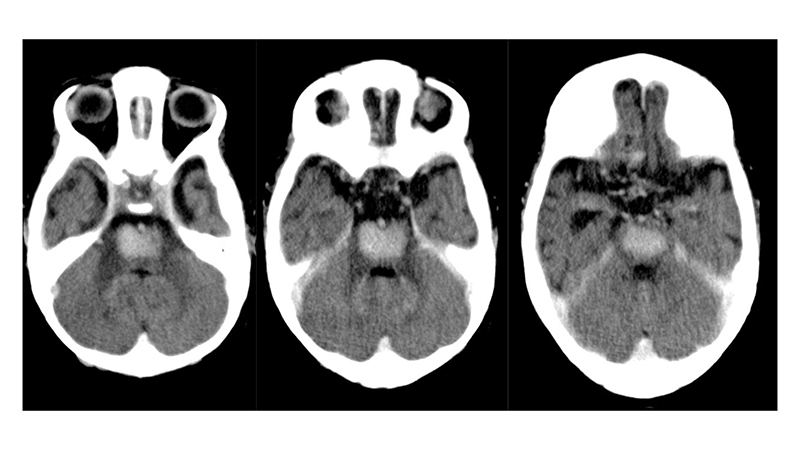

- Στην αξονική τομογραφία πρό μηνός, βλέπουμε υποφλοιώδεις και υποεπενδυματικές μικροαποτιτανώσεις αποτέλεσμα μικροϊσχαιμικών αλλοιώσεων εξαιτίας της φλεβικής υπερτάσεως. Συνυπάρχει αρχόμενη διάταση των κοιλιών.

- Στην αξονική τομογραφία εισαγωγής του, μετά σκιαγραφικό βλέπουμε επέκταση των μικροϊσχαιμικών αλλοιώσεων στο εγκεφαλικό στέλεχος με πρόσληψη σκιαγραφικού,